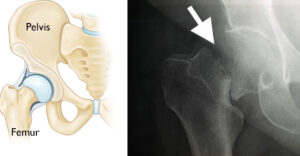

Hip fractures refer to breaks in the thighbone (femur) just below the hip joint, commonly affecting individuals aged 65 and older. Elderly women are particularly at risk due to osteoporosis.

The x-ray image on the right shows a hip fracture.